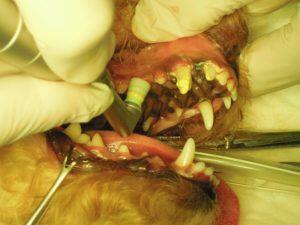

7.ポリッシングを行い、治療終了です。

8.治療後の右側外観です。

9.治療後の左側外観です。